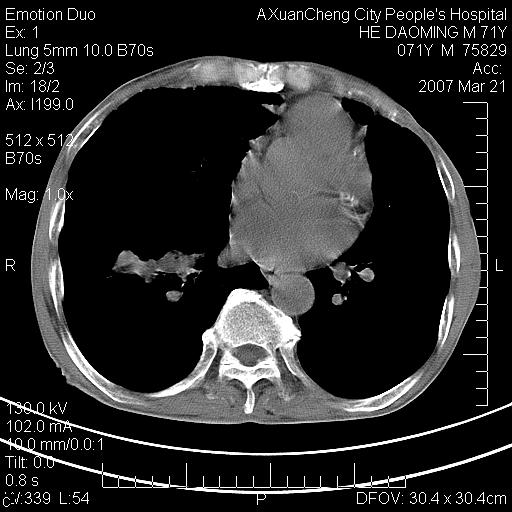

标题: CT7269:[原创] 咳嗽,咳痰,大家讨论右肺病变的部位 [打印本页]

标题: CT7269:[原创] 咳嗽,咳痰,大家讨论右肺病变的部位

1.慢支肺气肿 肺心病 肺大泡;2.叶间裂积液,前胸膜粘连

右侧相当于叶间软组织样密度ct值约50hu,请大家讨论是什么性者病变

右下肺大囊肿伴感染.肺气肿,肺大泡.

考虑:慢性支气管炎合并全小型肺气肿、肺大泡、间质纤维化、感染,右斜裂积液。

考虑慢支,肺气肿,肺大泡,间质纤维化;右侧斜裂液气胸考虑(可能因为肺大泡破裂破入斜裂所致).

考虑病变以右上中肺多发肺大泡为主并感染。请结合临床考虑慢支肺气肿,肺心病。

1双肺慢性支气管炎并全小叶型肺气肿肺大泡2间质性纤维化3右侧斜裂积液

考虑:慢性支气管炎合并右侧全小型肺气肿、肺大泡并感染、双肺间质纤维化,右斜裂积液。

考虑:慢性支气管炎合并右侧全小型肺气肿、肺大泡并感染、双肺间质纤维化,右斜裂积液。右侧斜裂液气胸考虑(可能因为肺大泡破裂破入斜裂所致).